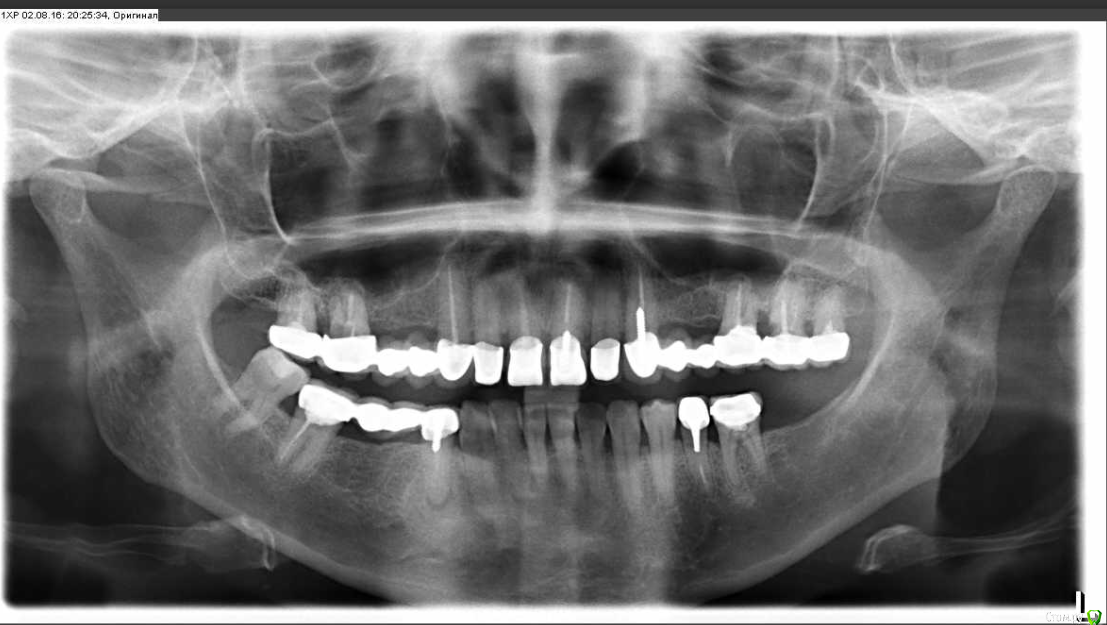

Ленусик333 Опубликовано 3 августа, 2016 Автор Поделиться Опубликовано 3 августа, 2016 Спасибо всем, кто отвечает.Да, это постоянные конструкции, уже прошедшие полную "подгонку", но пока они стоят на временном цементе. Так как меня мало устраивает внешний вид верхнего зубного ряда, а также я планирую заняться лечением десны (сильно ушедшей "вверх), то я попросила доктора поставить пока все на временный.Могу я попросить вас конкретизировать, что не так с лечением? Все зубы перед ортопедией мне пролечили.Также для меня важен вопрос: видна ли на рентгене ДО и ПОСЛЕ разница в состоянии десневой ткани сверху? В клинике отрицают факт изменения десны по их вине, хотя это произошло в процессе протезирования и по этому поводу мне собственно переделывали уже готовые коронки.Спасибо всем.Еще раз поставлю рентген до и после: Ссылка на комментарий

DmitrySH Опубликовано 3 августа, 2016 Поделиться Опубликовано 3 августа, 2016 Могу я попросить вас конкретизировать, что не так с лечением? Все зубы перед ортопедией мне пролечили. На данных снимках нет возможности оценить состояние мягких тканей. А состояние зубов до и после осталось одинаковымНужна ревизия каналов зубов :17, 16, 26, 27, 44, 47. состояние зубов 16, 27 ( на основании снимка) вызывает сомнения в их сохранении. 4 Ссылка на комментарий